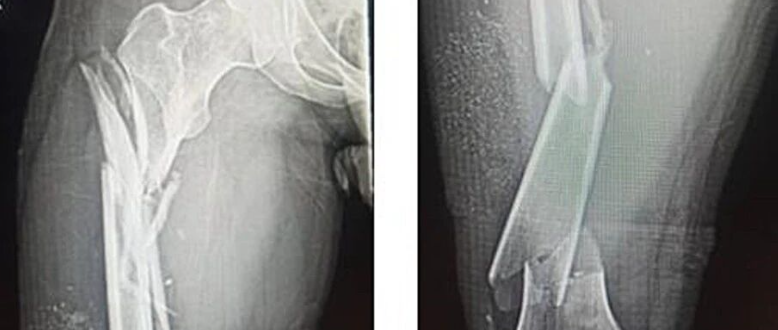

呼盆唤友 骨盆骨折手术专题课程

手外伤处理原则专题课程